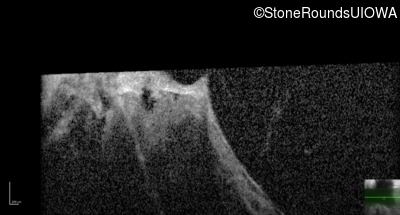

Optical Coherence Tomography - Right - Light Perception

Exemplar / OCT Stack

Infrared Fundus Photograph - Right - Light Perception

Exemplar